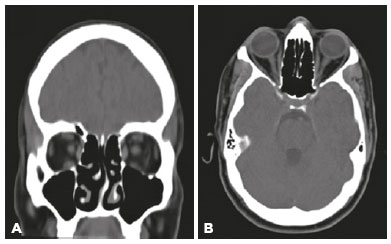

A 44-year-old generally healthy man who was referred for ophthalmologic consultation in a hospitalized institutional setting presented with a 5-day history of fever, double vision, and headache. The patient also reported fatigue, generalized muscle weakness, and loss of appetite for 1 wk. Several days before his admission, he had visited a healthcare practitioner and was sent home with antipyretic treatment. Owing to the absence of respiratory symptoms, COVID-19 was not suspected at that time. The patient had no known medical or ocular history, medications, or allergies. As his symptoms did not resolve, he was admitted to the hospital without any respiratory symptoms. Blood tests demonstrated mild lymphopenia (1.28 × 109/L), elevated C-reactive protein (92 mg/L), and D-dimer level (1.3 µg/mL) consistent with COVID-19. Lung auscultation and chest radiography indicated a bilateral pneumonia-like illness (Figure 1) that was asymptomatic. Computed tomography of the head showed no pathological findings (Figure 2). Reverse transcriptase-polymerase chain reaction (RT-PCR) was positive for SARS-CoV-2 in the patient’s first nasopharyngeal swab. Ophthalmologic examination, performed with complete personal protective equipment, revealed binocular diplopia and a limitation to abduction in the left eye. Orthophoria was noted in the right gaze. There was no additional cranial nerve involvement. Ophthalmologic examination, including pupillary response, anterior pole, and dilated fundus exam was otherwise unremarkable. Neurological examination showed normal results without any evidence of meningeal irritation. Lumbar puncture and magnetic resonance imaging were considered but not performed because symptoms resolved within 5 d of admission. Treatment included azithromycin and hydroxychloroquine for 5 d, as per the local infectious disease protocol. The patient was discharged to state-mandatory quarantine; 10 d thereafter, his condition had improved, and he tested negative for SARS-CoV-2.